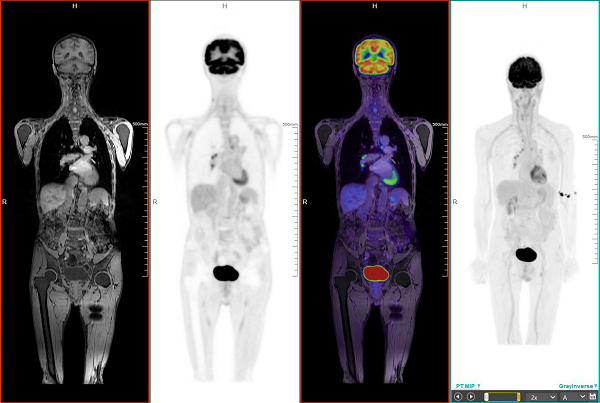

扫描案例:PET/MRI全身成像

PET/MRIPETMRI有机结合形成的一体化大型功能代谢与分子影像诊断设备,同时具备PETMRI的检查功能,不受呼吸运动、血管搏动等的影响,不会影响图像质量。检查时间比单独的PETMRI检查所需的时间短,达到最大意义上的优势互补,在软组织分辨率、检查的无创性等方面相比PET/CT更有优势。更为重要的是,其辐射剂量远远小于PET/CT,且MRI无电离辐射,是目前在细胞分子水平上进行人体功能代谢显像最先进的医学影像技术。

据了解,PET/MRI能对癫痫灶定位、老年痴呆、帕金森病等疾病进行检查,对癌症的扫描也更为精准,可对临床肿瘤的化疗以及治疗情况进行有效判断。心肌显像方面,PET/MRI被称为评估心肌活力的“金标准,是心肌梗塞血运重建治疗前的必要检查。目前深圳先进院主要利用PET/MRI进行动物影像实验,可以对药物药效或疾病的治疗提供重要临床意见。